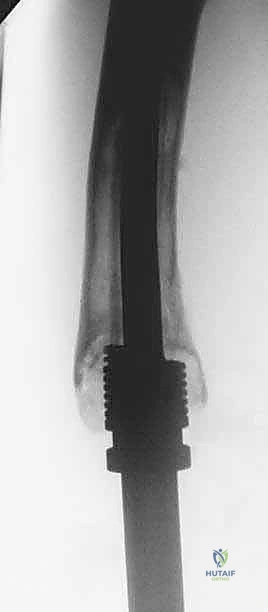

Canal Preparation and Implant Trialing

Following resection, the remaining host bone canal must be prepared. In pediatric patients, the intramedullary canal is often narrow, necessitating careful sequential reaming. We must balance the need for adequate implant stem diameter (for mechanical strength) against the risk of iatrogenic cortical perforation or fracture.

A trial prosthesis is assembled and inserted. This is a critical step to assess limb length, joint line restoration, and soft tissue tension. The knee (or relevant joint) is put through a full range of motion. We assess for patellar tracking, varus/valgus stability, and ensure there is no impingement of the expansion mechanism. If the soft tissues are excessively tight, a slightly shorter modular segment may be required; if too lax, a longer segment is chosen to ensure joint stability.

Definitive Fixation and Soft Tissue Reconstruction

Fixation in the pediatric skeleton is challenging. While press-fit, hydroxyapatite-coated stems are utilized to encourage biologic fixation and extracortical bone bridging, cemented stems remain the gold standard in many centers due to the immediate stability they provide in compromised, irradiated, or chemotherapy-affected bone.

If cementing, a cement restrictor is placed, the canal is pulsatile-lavaged and dried, and third-generation cementing techniques (vacuum mixing, retrograde injection) are employed. The definitive prosthesis is impacted into place, ensuring correct version.